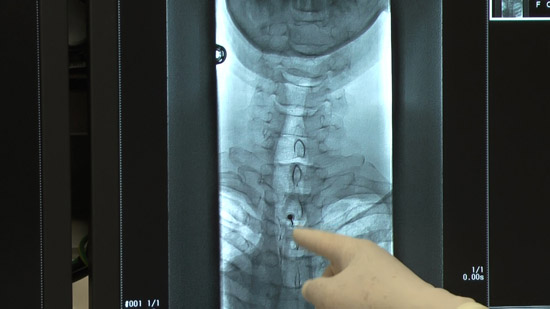

(3)Insert a guide needle (22-gauge needle) just in front of the dura mater

(4)Insert a pencil-point puncture needle into the dura mater

(5)Check the leakage of the cerebrospinal fluid